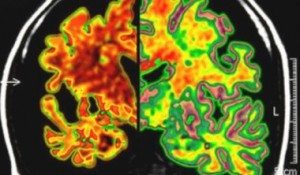

alzheimer-parkinson-beyinDejeneretif sinir sistemi hastalıklarında beyin dokusunun ölümünü engelleyen ilk kimyasal bileşimin keşfi, Alzheimer, Parkinson ve Huntington hastalıklarının tedavisi açısından tıp dünyasında heyecan yarattı. Hastaların tedavi amacıyla alabileceği bir ilacın geliştirilmesi için daha fazla araştırma yapılması gerekiyor. Fakat bilim insanları, geliştirilecek bu ilacın Azheimer, Parkinson, Huntington ve benzeri hastalıkların tedavisinde kullanılabileceğini belirtiyor. İngiltere’deki Leicester Üniversitesi’nde fareler üzerinde yapılan deneylerde, beyni süngere çeviren ”prion hastalıklara” bağlı beyin hücresi ölümlerinin engellenebileceği görüldü.

beyin-sembolAraştırmacıların kullandığı kimyasal bileşim bu savunma mekanizmasının devreye girmesini ve dejenerasyonu engelliyor. Science Translational Medicine dergisinde yayımlanan araştırma, beyni süngere dönüştüren prion hastalıklara sahip olan farelerde ciddi hafıza ve hareket kaybı görüldüğünü ve 12 haftada öldüklerini ortaya koydu. Fakat bu kimyasal bileşimin verildiği farelerde beyin dokusunda hiçbir kayıp görülmedi.